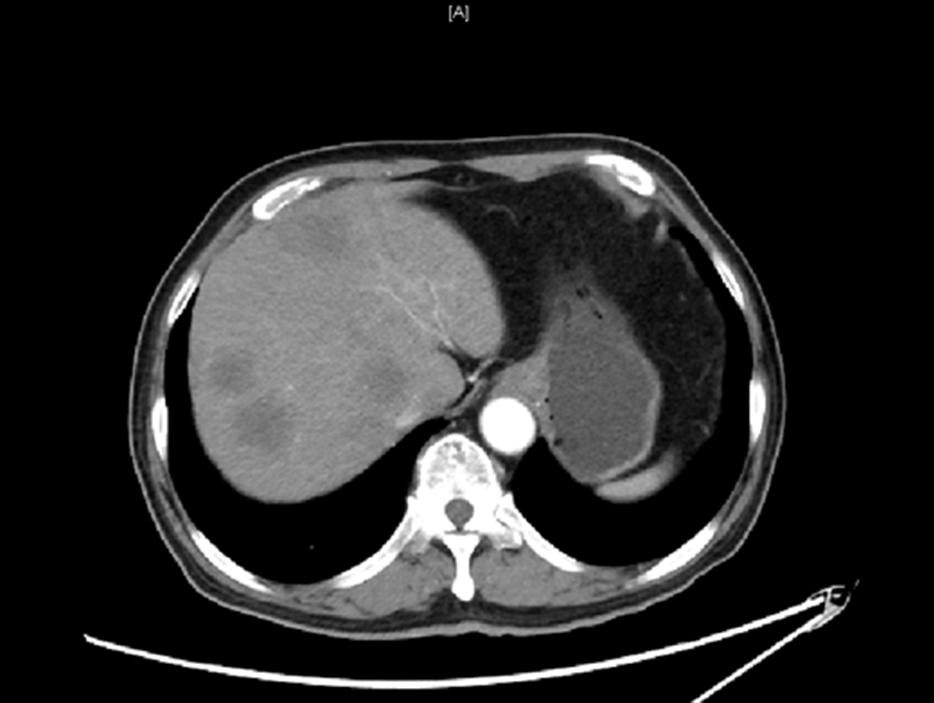

2019.11.18 腹部CT: 肝脏多发结节(图2),考虑转移。

图2. 腹部CT(2019.11.18)